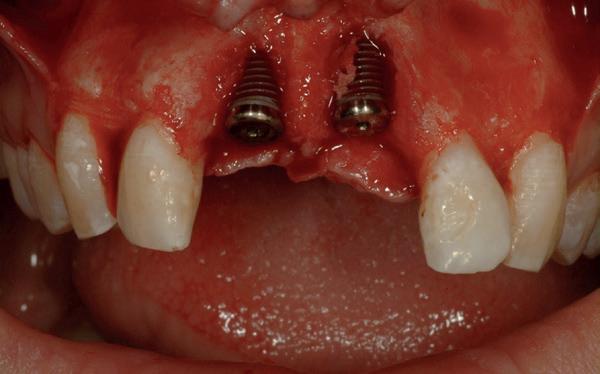

In het onderfront werd autoloog bot geoogst uit de kin regio ten behoeve van augmentatie (afbeelding

9. Botopbouw onderfront

9). In de bovenkaak werd bilateraal een sinuslift uitgevoerd. Aansluitend werden in beide kaakhelften implantaten geplaatst (afbeelding 10).